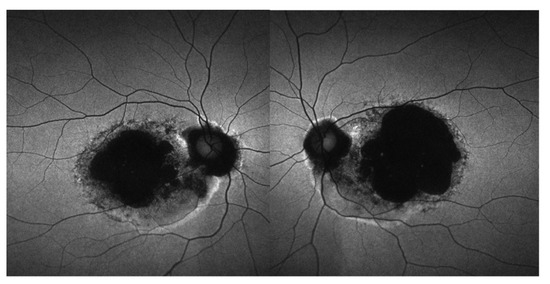

3.5. Retinal Imaging

3.6. Longitudinal Data